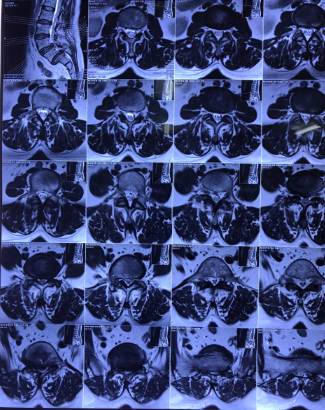

Hình ảnh: Cộng hưởng từ và X Quang bệnh nhân trước phẫu thuật

Hình ảnh: Cộng hưởng từ và X Quang bệnh nhân trước phẫu thuật